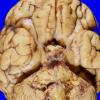

NEOPLASMS (HEMATOLYMPHOID)

Granulocytic Sarcoma (2)